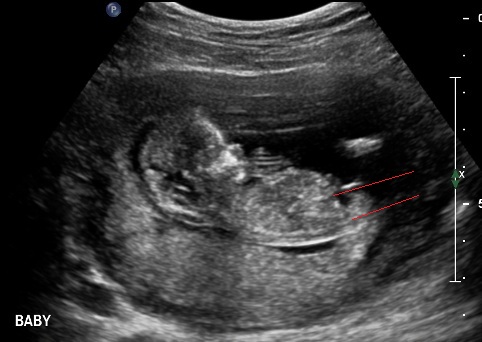

Well went for my scan today, baby was very photogenic! I was exactly 13 weeks.

Not sure what i feel, i am so in love with this baby already. Its funny coz even tho I swayed i am realy not bothered about gender, will not be finding out gender until birth but still would love guesses. Tech gave me her feeling what she thought.

Attachment 3732Attachment 3733Attachment 3734